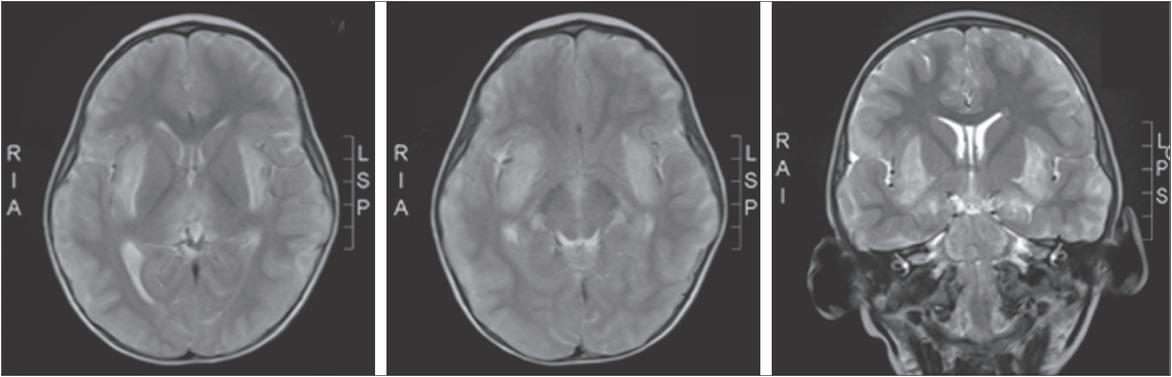

Brain MRI in a child with acute necrotizing encephalopathy and a positive RANBP2 gene mutation. Brain MRI showing increased T2 hyperintensity of basal ganglia (A, B, and C).

10M-3yesnoacute necrotizing encephalopathy; generalized seizures; spasticity; coma and death; brain MRI: symmetric thalamic hyperintense lesions3 yearsRANBP2pathogenic: c.1754C>T, p.(Thr585Met)acute infection-induced encephalopathy-type 3, OMIM: 608033